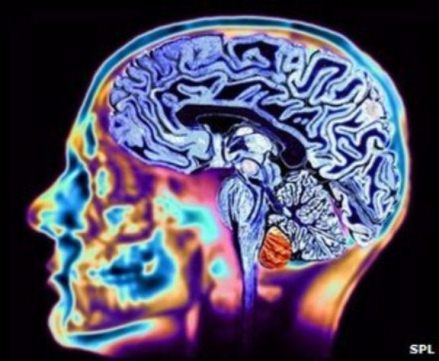

Image of an MRI scan,used to detect Huntington's disease.

Image of an MRI scan of the brain.